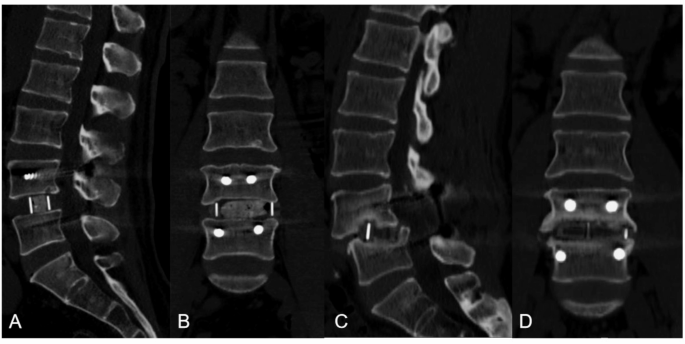

Cage subsidence diagnostic criteria

As per the criteria established by Pisano AJc22, cage subsidence was identified if postop.erative imaging revealed the fusion device penetrating the upper or lower endplate by a depth of 2 mm or more at any postoperative time point.

Measurement Method: Postoperative follow-up CT images in the sagittal plane were reviewed for all patients. The slices showing cage subsidence were identified, and the maximum distance between the cage and the endplate was measured, with the largest value recorded as the subsidence depth. This assessment was performed by two trained specialists, and discrepancies were resolved by consulting a third senior spine surgeon. Patients with subsidence were categorized into the subsidence group, while the rest were classified as non-subsidence. Illustrative examples of cage subsidence are shown in Fig. 2.

(A) and (B): No cage subsidence occurred. (C) and (D): Cage subsidence occurred.